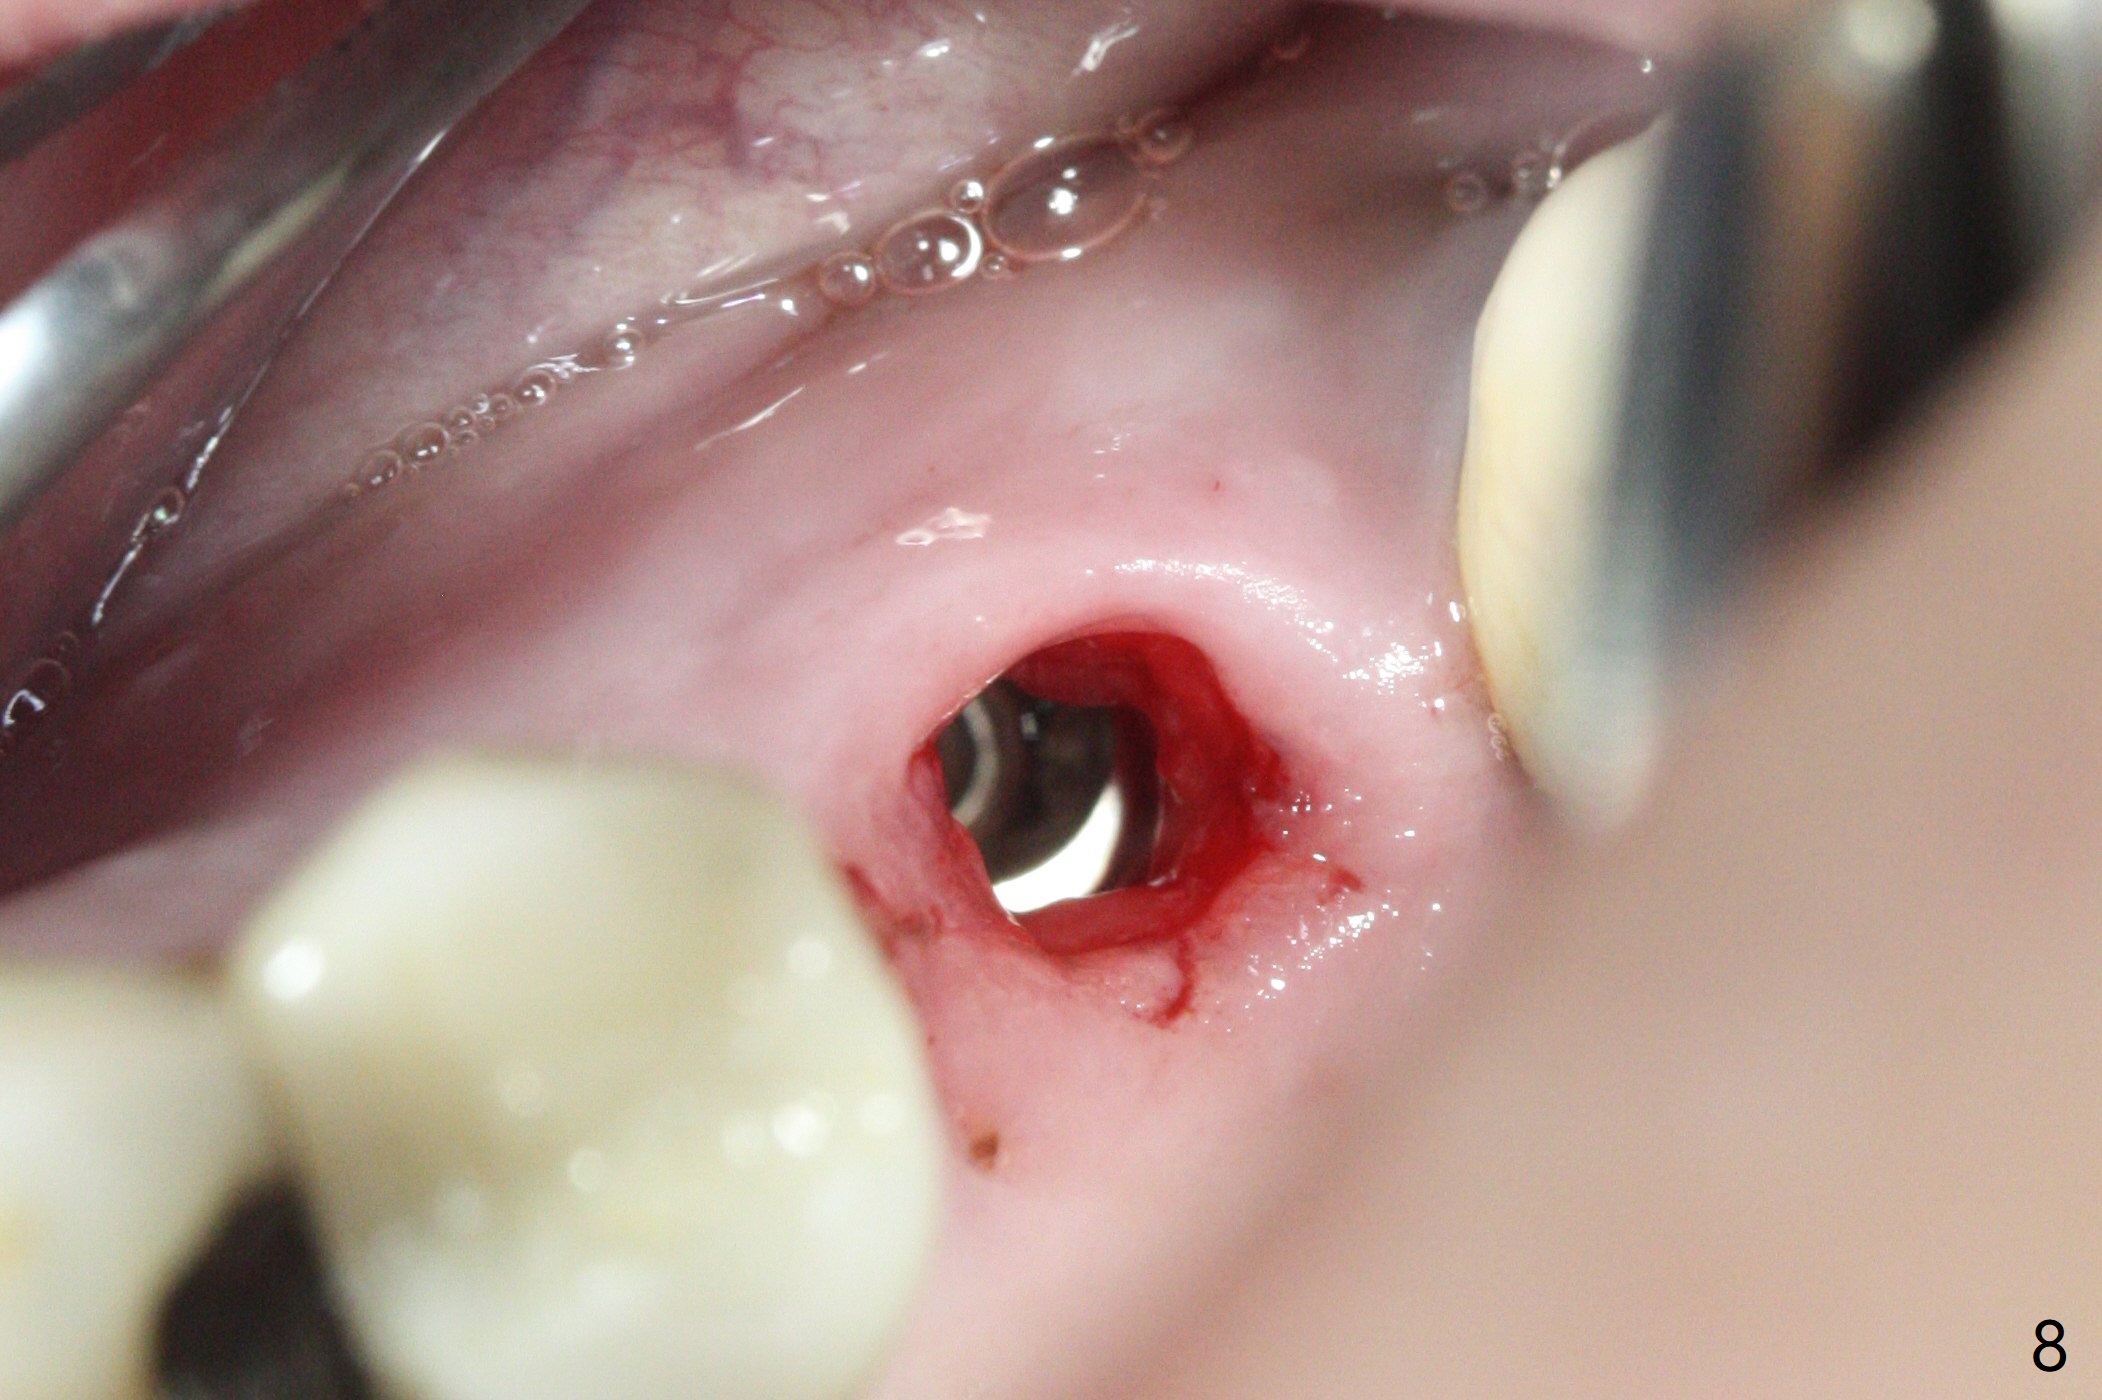

Initial osteotomy in the septum of the tooth #14 is 9 mm, approximately 2 mm from the sinus floor (Fig.1).  Subsequent osteotomy depth is 11 mm, followed by insertion of a 4.5x11 mm dummy implant (Fig.2).  After use of Magic Drill (MD) 4.8 mm for 9 mm, a 5x11 mm IBS implant is placed with sinus lift without additional bone graft (Fig.3 *).  In contrast, autogenous bone (from MD) and Vanilla Graft are meticulously placed in the remaining socket (+) before and after placement of a 6.5x5.7(2) mm abutment.  An immediate provisional is fabricated to close the sockets.  There is buccal tenderness 1-3 months postop.  There is distopalatal implant thread exposure.  A healing abutment (5.5x2 mm) is placed.  CT confirms thin buccal plate (Fig.4,5).  It appears that the implant should have been as palatal as possible.  The tenderness remains for the next 2 weeks.  When the healing abutment is removed, the implant seems to have been placed shallow, ~ 1 mm subgingival (Fig.6).  With local anesthesia, the implant is reversed to clean the coronal threads with Titanium brush and copious irrigation (Fig.7).  The implant is then placed ~4 mm subgingival (Fig.8) and slightly subcrestal (Fig.9,10).  It appears that the postop bone loss (Fig.9 *, as compared Fig.1,2) makes the implant look to be placed too shallow.  When the implant is being placed deeper, the buccal plate feels intact.  The early periimplantitis is apparently due to postop bone loss more than buccal placement, although certain degree of buccal bone resorption must occur.  A 6x4 mm healing abutment is placed.  Left facial swelling develops 2 days post implant elevation (Fig.11,12, as compared to preop (Fig.13)).  The left maxillary sinus cloud (Fig.12) appears to be a false positive finding, since the same feature exists prior to implant elevation (Fig.13).  Both sinuses look clear prior to implant elevation (Fig.14).  Amoxicillin switches to Augmentin and Flagyl, since the patient is reluctant to have the implant removed.  Finally the sinus infection is under control.  The patient feels left facial swelling 9 months postop (5 months post elevation) and reports left nasal discharge ~ 1 month earlier.  There is mild buccal plate tenderness.  The implant seems to be buccally placed (Fig.15,16), although there is no significant change radiographically (Fig.17).  The implant is removed with bone graft (Fig.18 *).  To avoid complication and failure, an immediate implant at the upper 1st molar should be short and placed deep.